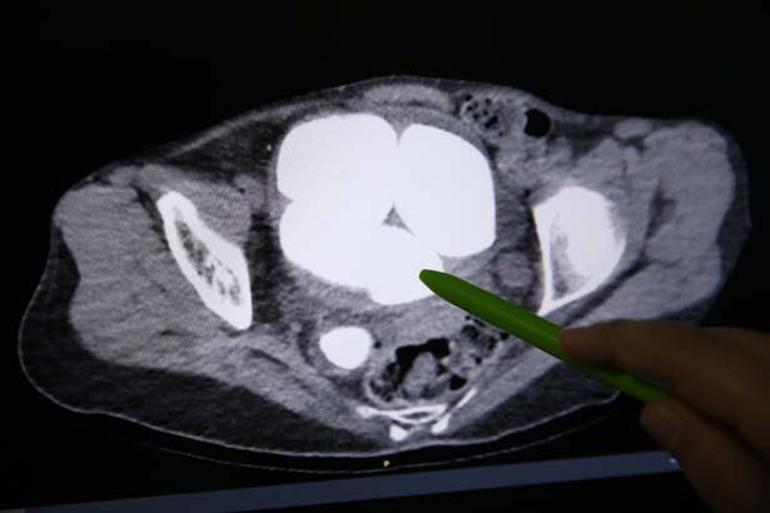

Opr. in der Abteilung für Urologie. Dr. Bei den von Süleyman Çankaya durchgeführten Untersuchungen wurden 6 Steine, der kleinste mit 2 Zentimetern und der größte mit 9 Zentimetern, in der Blase und den Harnwegen des Patienten entdeckt.

Üroloji Bölümünde Opr. Dr. Süleyman Çankaya tarafından yapılan tetkiklerde, hastanın mesanesi ve idrar kanalında en küçüğü 2, en büyüğü 9 santimetre olan 6 taş tespit edildi.